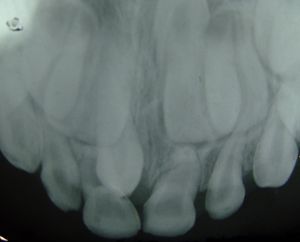

과잉치는 서로 다른 각도에서 두 개의 치과 X-ray를 촬영하여 감지할 수 있다. 구강 내 X-ray(구강 내에서 촬영하는 X-ray)와 파노라마 방사선 사진이 그 예이다. 그러나 이러한 X-ray는 2D이므로 치아의 3D 모습을 정확하게 나타내지 않는다.[2]